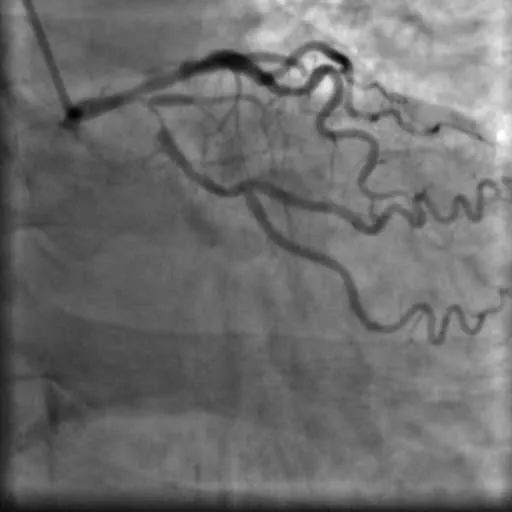

入院后,杨大爷很快在心血管介入中心进行了冠状动脉造影及血管内超声检查术,结果显示:左主干末端至前降支近段,回旋支开口都有严重狭窄且伴钙化。如果再推迟入院几天,很有可能发生猝死。

造影及血管内超声显示两枚支架均贴壁良好,前降支及回旋支开口管腔狭窄显著改善,前向血流良好。

造影图